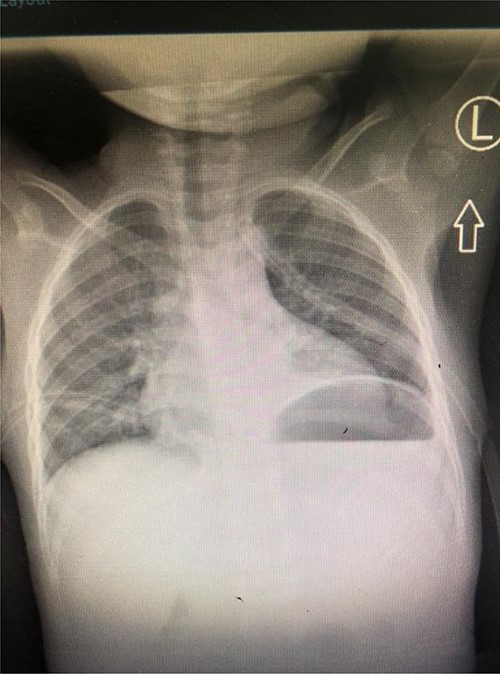

A total of 48 hours post tube thoracostomy patient had no drainage with complete resolution upon control X-ray (Fig. 4). She was then discharged and attended our outpatient department. She had an optimal recovery.

Control Chest X-ray showing resolution of the chylothorax with thoracostomy tubes in situ.